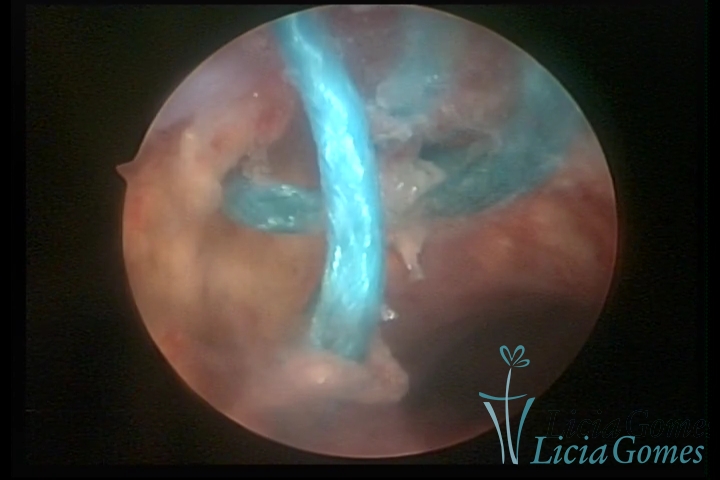

Cavity with Mirena®, being removed under direct view